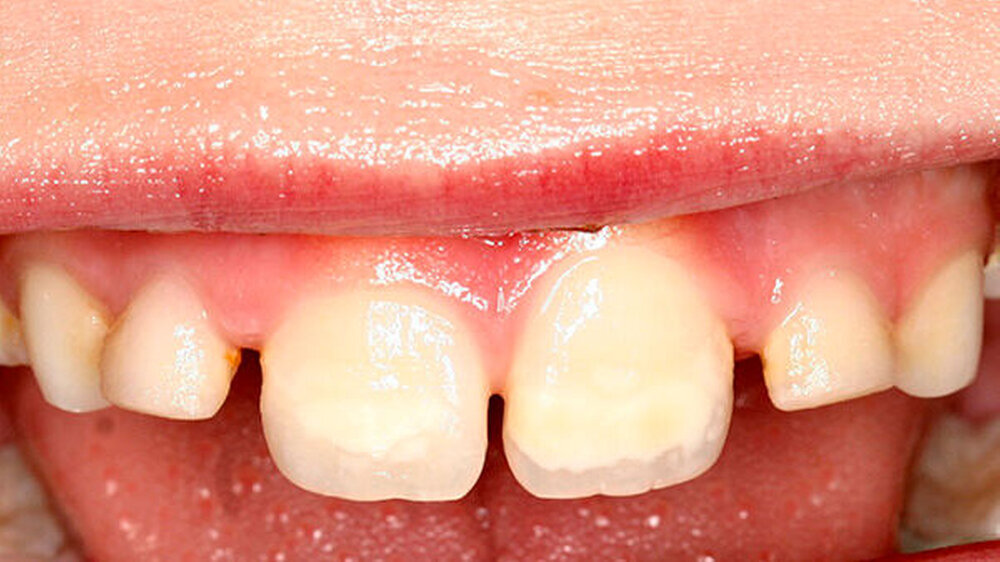

Zusätzlich zeigte der mesio-palatinale Höcker einen deutlichen Schmelzeinbruch (Abbildung 1). Die generelle Mundhygiene war nur mäßig, da insbesondere an den Glattflächen (obere mittlere Inzisivi) auch ohne Anfärbung deutlich sichtbarer Biofilm aufzufinden war (Abbildung 2). Die Zähne 26, 36 und 46 wiesen kaum sichtbare Opazitäten auf, sie waren alle versiegelt (nicht dargestellt).

Aufgrund der Verteilung der Opazitäten und Schmelzeinbrüche im Gebiss entsprach die Erkrankung zum Zeitpunkt der Untersuchung der Molaren-Inzisiven-Hypomineralisation (MIH). Erkrankt waren hier die typischen Index-Zähne: Sechsjahr-Molaren (in unterschiedlicher Intensität) sowie die bleibenden Schneidezähne.

Die klinischen Besonderheiten bei dieser Patientin entsprechen kaum dem üblichen Bild der Dentalfluorose, bestenfalls die lateralen Bereiche mittleren oberen Inzisivi weisen eine auch bei der Dentalfluorose aufzufindende wolkige Struktur auf. Es überwiegt jedoch die flächige Opazität, die eher für die MIH typisch ist.